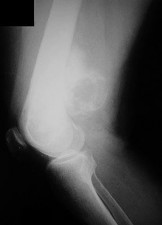

A 15-year-old male presents with deep knee pain awakening him at night. Radiographs show a permeative destructive lesion in the distal femoral metaphysis with a 'sunburst' periosteal reaction and Codman's triangle.

Biopsy confirms high-grade conventional osteosarcoma. What is the most critical prognostic factor for long-term overall survival in this patient?

Explanation

For localized high-grade osteosarcoma, the most important prognostic indicator is the histologic response to neoadjuvant chemotherapy. This is evaluated during the definitive resection. A 'good response' is typically defined as greater than 90% or 99% tumor necrosis. Patients who achieve this level of necrosis have a significantly improved disease-free and overall survival rate compared to 'poor responders' who have extensive viable tumor cells remaining.